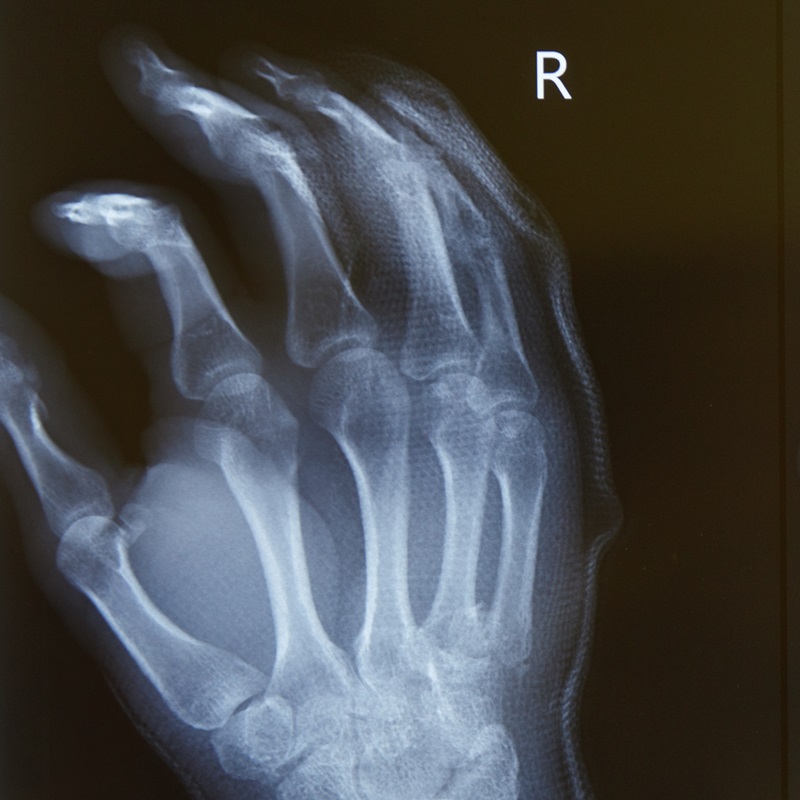

Кисть людини — надзвичайно делікатний орган зі складною структурою, який у повсякденному житті зазнає великих функціональних навантажень. Суглоби, кістки, м’язи, зв’язки, сухожилки, нерви і судини кисті часто травмуються або страждають від захворювань. Консервативне лікування допомагає не завжди, а оперативне вимагає особливого підходу.

Лише огляду на первинному прийомі замало, щоб точно встановити діагноз. Необхідно пройти додаткові обстеження, які візуалізують ушкодження, допоможуть визначити його ступінь та зону поширення на сусідні тканини.

Під час хірургічного втручання кисть пацієнта розміщена під мікроскопом. Відновлення сухожиль, судин та нервів відбувається за допомогою мікроінструментів. У Клініці МЕДІКОМ також проводять хірургічні операції кисті під рентгенологічним або УЗД контролем.